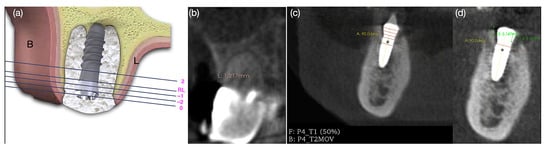

A cone beam computed tomography (CBCT) scan was performed using buccal retractors to isolate the soft tissue contours, with a field of view (FOV) of 7 × 15 cm, a 0.3 mm voxel size, and a resolution of 0.5 mm (scan time: 20 s, 14 bits grayscale) using an i-CAT Classic (Imaging Sciences International, Inc., Hatfield, PA, USA). The CBCTs were performed before tooth extraction, after the implant surgery (T1) and 4 months (T2) post-implant placement. To align the original DICOM data from the T1 and T2 CBCTs scans, a superimposition was performed following the methodology previously described in the literature [21], by the OnDemand3D software (Version 1.0.9.3223, CyberMed Inc., Seoul, Republic of Korea) and transformed into the (.gipl) format using the ITK-SNAP software (version 3.6.0, www.itksnap.org, accessed on 30 September 2020) to enable proper superimposition in the Slicer software (version 5.0.2, www.slicer.org, 30 September 2020). The linear measurements were made using the same reference points, in which the vertical and horizontal measurements followed the parallelism of a perpendicular line drawn on the implant. A horizontal reference line (RL) was determined at the implant platform with the smooth/rough surface junction [3]. A single-blinded and calibrated examiner performed all the measurements (Figure 1). Horizontal width hard tissue alteration changes between the T1 and T2 of the lingual/palatal and buccal bone wall (HBT) at five levels were measured: the RL and at 0 mm, −1 mm, and −2 mm above the RL; and 2 mm below the RL. The buccal and lingual bone level changes were determined by variation on vertical bone height between baseline (T1) and 4 months (T2) after implant placement (ΔVBH T1-T2). The buccal vertical soft tissue thickness was measured prior to tooth extraction using a CBCT scan. One of the major advantages of using a 3D Slicer is the ability to achieve transparency between T1 and T2 slices, allowing the same reference marking, traced only once, to be reproduced consistently across both analysis time points.

Figure 1. (a) Illustrative diagram of horizontal bone thickness measurements from the reference line (RL); (b) vertical soft tissue measurement; (c) horizontal reference lines and superimposition of the DICOM (Digital Imaging and Communications in Medicine) of the two CBCT scans on T1 and T2; (d) vertical reference lines at the lingual and buccal bone wall.